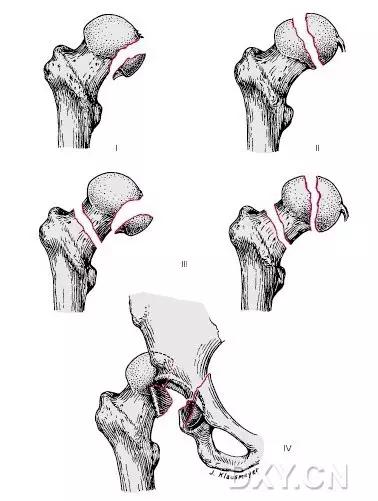

6. Pipkin 骨折

股骨头骨折。1957 年,Pipkin G 在文献中对其进行详细的描述并分型,至今仍在很多文献中被采用。

(来源:radiopaedia)

-

Ⅰ型:骨折块在圆韧带的下方;

Ⅱ型:骨折块在圆韧带的上方;

Ⅲ型:Ⅰ、Ⅱ两型任意一种伴股骨颈骨折;

Ⅳ型:Ⅰ、Ⅱ两型任意一种伴髋臼骨折 。